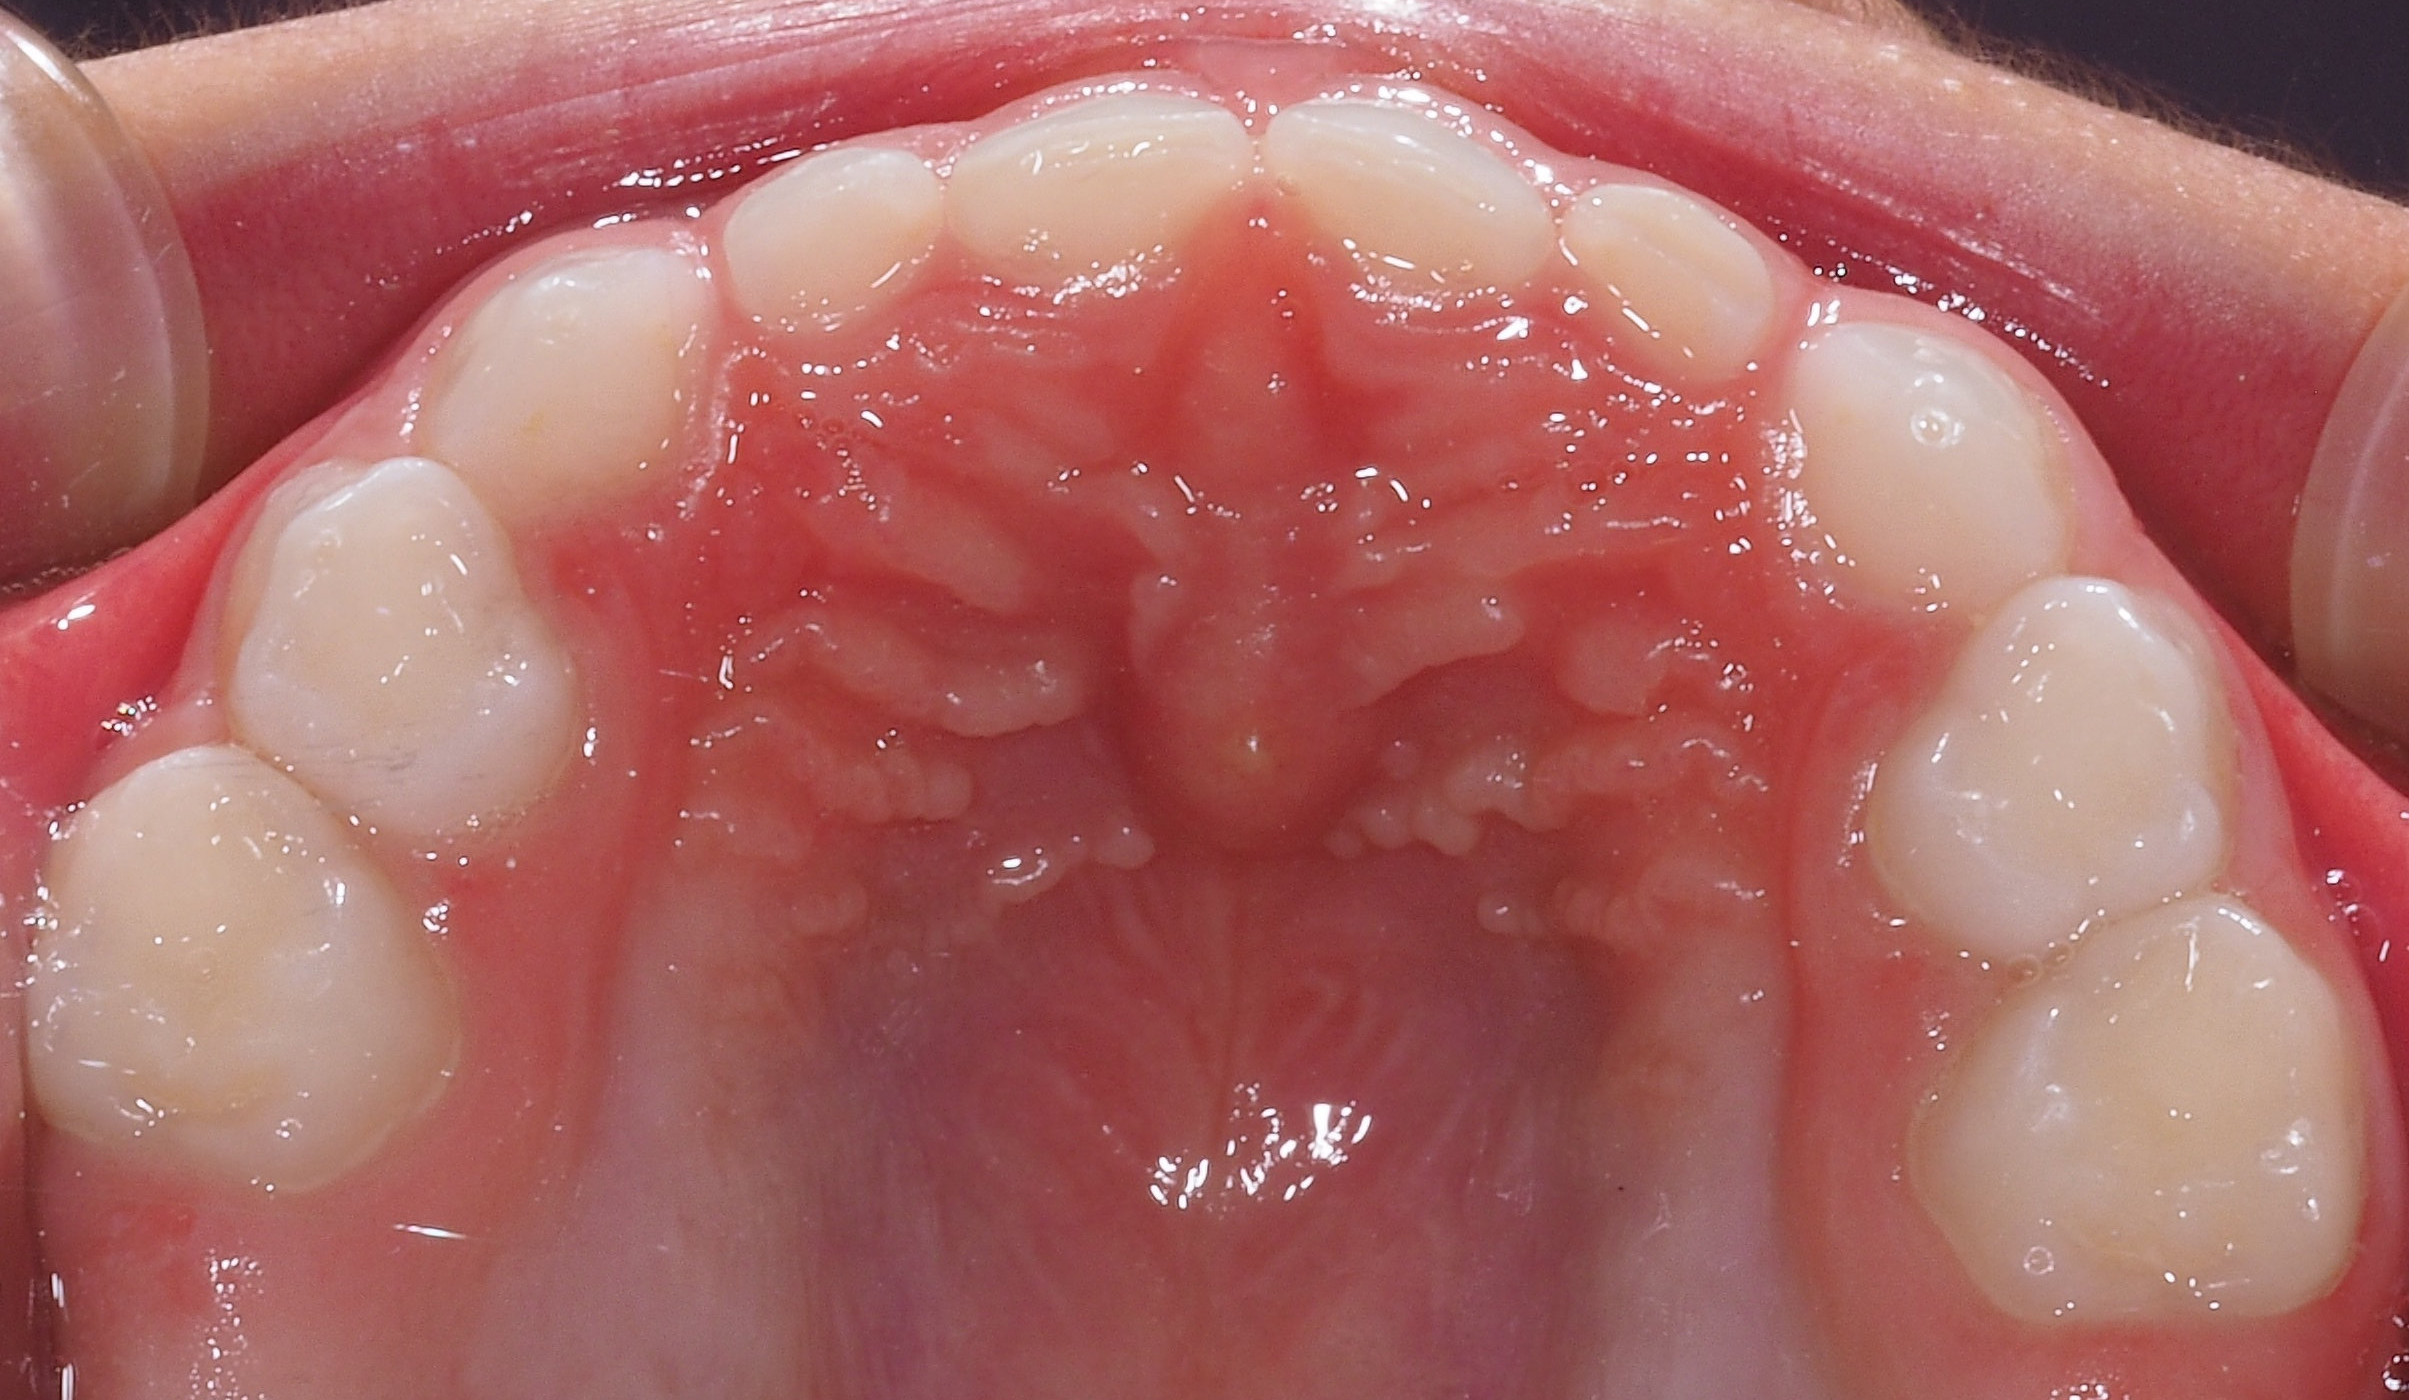

La ricrescita dei denti nei bambini: quando erompono i denti permanenti?

Con la perdita dei denti da latte, molti genitori ci chiedono quando avviene di solito la ricrescita dei denti nei bambini. Vediamo insieme quali sono le fasi di sviluppo della dentizione nei pazienti più piccoli, e come monitorare il processo di crescita.

L’eruzione dei denti permanenti avviene in contemporanea alla fase di permuta e inizia intorno ai 6-7 anni d’età, con la comparsa dei primi molari e degli incisivi centrali inferiori.

Verso gli 8 anni compaiono gli incisivi centrali superiori, mentre quelli laterali spuntano entro il 9° anno d’età. La ricrescita dei denti continua con l’eruzione dei primi e secondi premolari, che avviene di solito tra i 9 e i 10 anni, dei secondi molari e dei canini, che si sviluppano intorno ai 12-14 anni. La crescita del terzo molare invece – o dente del giudizio – avviene tra i 17 e i 25 anni, ma può anche non verificarsi affatto.

La fase di dentatura mista – in cui sono presenti sia i denti da latte che quelli permanenti – rappresenta un momento estremamente importante per lo sviluppo delle arcate dentarie. È necessario quindi fissare delle visite periodiche dal dentista, in modo da individuare e correggere precocemente eventuali problemi scheletrici e masticatori.